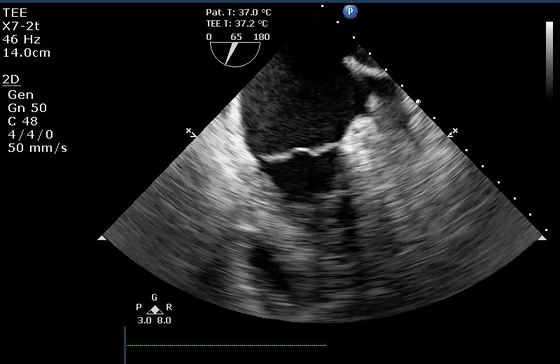

10、经食管超声图像伪像

虽然上面介绍的主要集中在常规经胸超声心动图,但上述伪像也经常在经食管超声心动图中遇到。图10显示了经食管超声心动图中一些常见的伪像。在这方面最相关的临床情况是(1)排除LAA中的血栓(图10E和10F)和(2)排除主动脉夹层(图10G和10H)。

(D)疑似两个平行的主动脉(Ao)的镜像伪影(星号)。注意血流也产生镜像伪像(视频17)。

(E)左心耳疑似血栓的混响伪影。从多个角度(见图F)进行分析证实存在华法林嵴的混响(星号),而不是真正的血栓(视频18-19)。

(G)在升主动脉(视频20)中延伸的钙化窦管连接(箭头)的旁瓣伪影(箭头)不应被误解为夹层。

(H)同样,升主动脉中的回声可能会被误解为夹层。